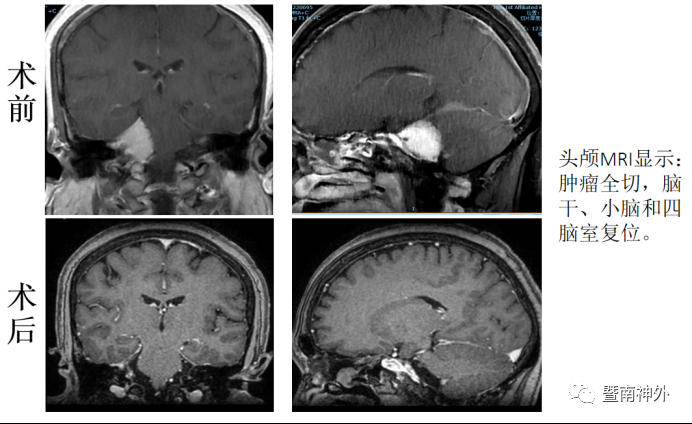

术后半年复查